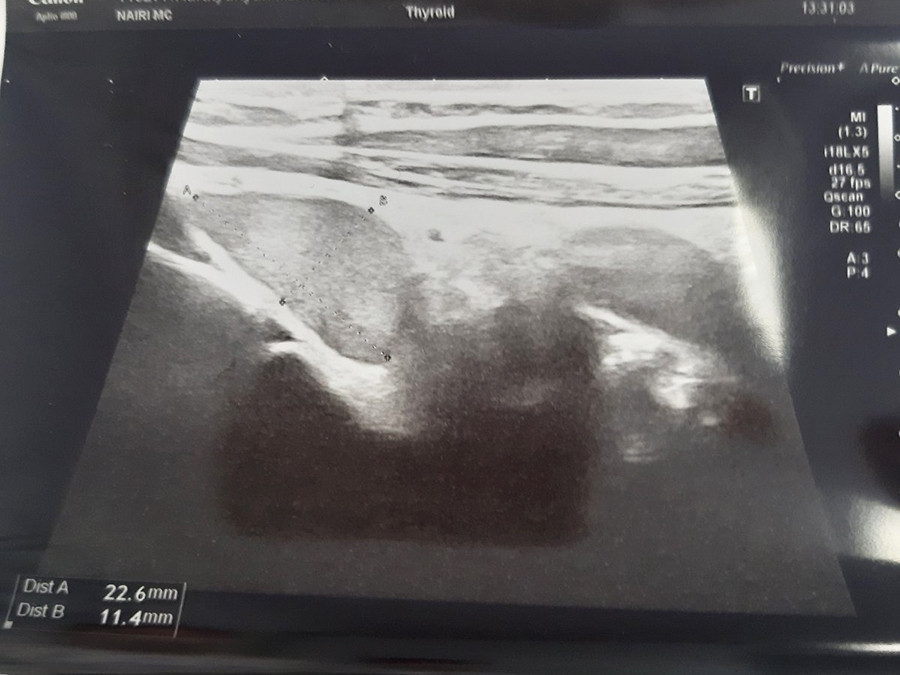

«Նաիրի» ԲԿ ընդունարան էր դիմել 30 տարեկան կին` ոսկրային համակարգի քաղցկեղի կասկածով: Ուղղորդվել էր օնկոօրթոպեդի մոտ, ով պետք է իրականացներ բաց բիոպսիա` ախտորոշման հաստատման համար: Սակայն երկարատև զննումից, մանրամասն անամնեզ հավաքելուց հետո օնկոօրթոպեդի մոտ առաջացավ կասկած, որ պացիենտի մոտ առկա է հարվահանաձև գեղձի հետ կապված խնդրով պայմանավորված օստեոպորոզ: Գործընթացին միացավ էնդոկրին վիրաբույժը, կատարվեց ՈՒՁ հետազոտություն, պարանոցի և կրծքավանդակի համակարգչային տոմոգրաֆիա, ինչի արդյունքում հայտնաբերվեց աջ ստորին հարվահանագեղձի բավականին մեծ չափերի` մոտավորապես 25 մմ ադենոմա, որից հետո պացիենտին նախապատրաստեցին և կատարեցին վիրահատություն. հեռացվեց ախտահարված հարվահանագեղձը:

Ցավոք Հայաստանում հարվահանաձև գեղձի ադենոմաների ախտորոշման ոսկե ստանդարտ համարվող հարվահանաձև գեղձի սցինտիգրաֆիան դեռևս առկա չէ, բայց մոտ ապագայում սպասվում է: Ներկայացված կլինիկական դեպքի պարագայում մասնագետները վստահ էին, որ առկա է հարվահանաձև գեղձի ադենոմա, թեև կար մտավախություն, որ նրա տեղեկայման հայտնաբերման հարցում հնարավոր են որոշակի խնդիրներ: Բարեբախտաբար, թե՛ ՈՒՁՀ, թե՛ ՀՏ հետազոտությունները հնարավորություն տվեցին հայտնաբերել ախտահարված օրգանն ու նրա տեղակայումը, իրականացնել համապատասխան բուժում և ստանալ ցանկալի արդյունքներ: